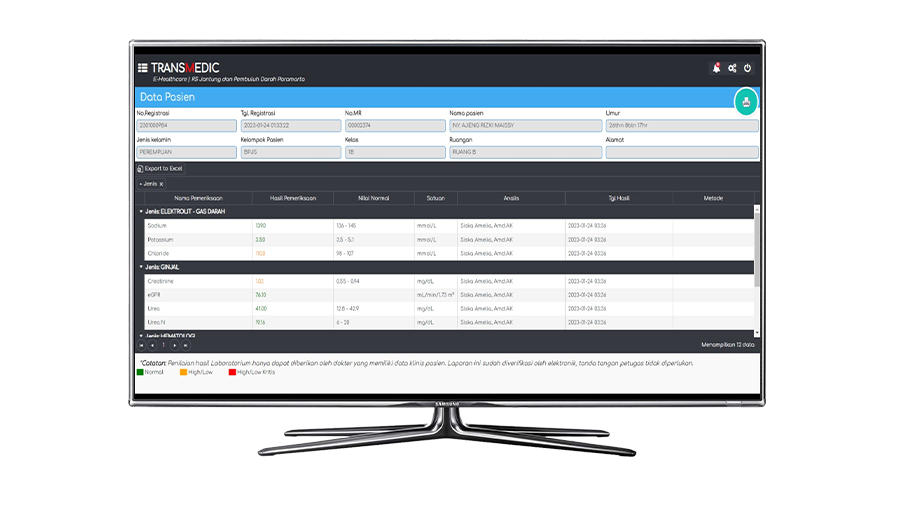

LIS adalah sistem yang digunakan untuk mengelola informasi yang dihasilkan oleh proses laboratorium medis. Sistem informasi laboratorium ini bertujuan untuk memudahkan pelaksanaan dan pemantauan kinerja laboratorium.

Lebih Lanjut